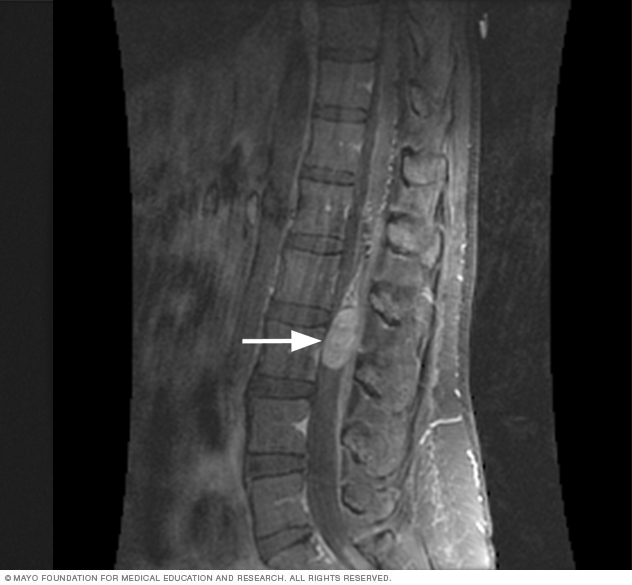

Spinal magnetic resonance imaging

Magnetic resonance imaging uses a powerful magnetic field and radio waves to make pictures of the inside of the body. This test also is called an MRI. A spinal MRI can make detailed pictures of your spinal cord. MRI is usually the preferred test to detect spinal cord tumors.

A member of your healthcare team might put a dye into a vein in your hand or arm during the MRI. This dye, called a contrast agent, helps make clearer pictures.